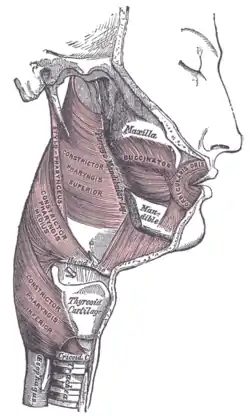

| |

The pharyngeal muscles are a group of muscles that form the pharynx, which is posterior to the oral cavity, determining the shape of its lumen, and affecting its sound properties as the primary resonating cavity.

The pharyngeal muscles (involuntary skeletal) push food into the esophagus. There are two muscular layers of the pharynx: the outer circular layer and the inner longitudinal layer.

The outer circular layer includes:

During swallowing, these muscles constrict to propel a bolus downwards (an involuntary process).

The inner longitudinal layer includes:

During swallowing, these muscles act to shorten and widen the pharynx.